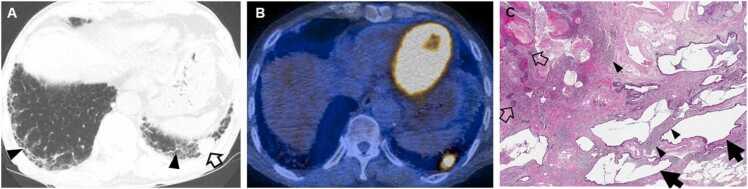

Connective tissue diseases (CTDs) demonstrating features of interstitial lung disease (ILD) include systemic lupus erythematosus (SLE), rheumatoid arthritis (RA), systemic sclerosis (SSc), dermatomyositis (DM) and polymyositis (PM), ankylosing spondylitis (AS), Sjogren syndrome (SS), and mixed connective tissue disease (MCTD). On histopathology of lung biopsy in CTD-related ILDs (CTD-ILDs), multi-compartment involvement is an important clue, and when present, should bring CTD to the top of the list of etiologic differential diagnoses. Diverse histologic patterns including nonspecific interstitial pneumonia (NSIP), usual interstitial pneumonia (UIP), organizing pneumonia, apical fibrosis, diffuse alveolar damage, and lymphoid interstitial pneumonia can be seen on histology in patients with CTD-ILDs. Although proportions of ILDs vary, the NSIP pattern accounts for a large proportion, especially in SSc, DM and/or PM and MCTD, followed by the UIP pattern. In RA patients, interstitial lung abnormality (ILA) is reported to occur in approximately 20-60% of individuals of which 35-45% will have progression of the CT abnormality. Subpleural distribution and greater baseline ILA involvement are risk factors associated with disease progression. Asymptomatic CTD-ILDs or ILA patients with normal lung function and without evidence of disease progression can be followed without treatment. Immunosuppressive or antifibrotic agents for symptomatic and/or fibrosing CTD-ILDs can be used in patients who require treatment.

表现为间质性肺疾病(ILD)特征的结缔组织病(CTD)包括系统性红斑狼疮(SLE)、类风湿关节炎(RA)、系统性硬化症(SSc)、皮肌炎(DM)和多发性肌炎(PM)、强直性脊柱炎(AS)、干燥综合征(SS)以及混合性结缔组织病(MCTD)。在CTD相关ILD(CTD-ILD)的肺活检组织病理学检查中,多部位受累是一个重要线索,若出现这种情况,应将CTD列为病因鉴别诊断的首要考虑。CTD-ILD患者的组织学检查可见多种组织学模式,包括非特异性间质性肺炎(NSIP)、寻常型间质性肺炎(UIP)、机化性肺炎、肺尖纤维化、弥漫性肺泡损伤和淋巴细胞间质性肺炎。尽管ILD的比例各不相同,但NSIP模式占很大比例,尤其是在SSc、DM和/或PM以及MCTD中,其次是UIP模式。据报道,RA患者中约20%-60%会出现间质性肺异常(ILA),其中35%-45%的患者CT异常会进展。胸膜下分布以及基线时ILA受累程度较高是与疾病进展相关的危险因素。无症状的CTD-ILD或ILA且肺功能正常且无疾病进展证据的患者可以不进行治疗而进行随访。有症状的和/或纤维化的CTD-ILD患者若需要治疗,可使用免疫抑制剂或抗纤维化药物。